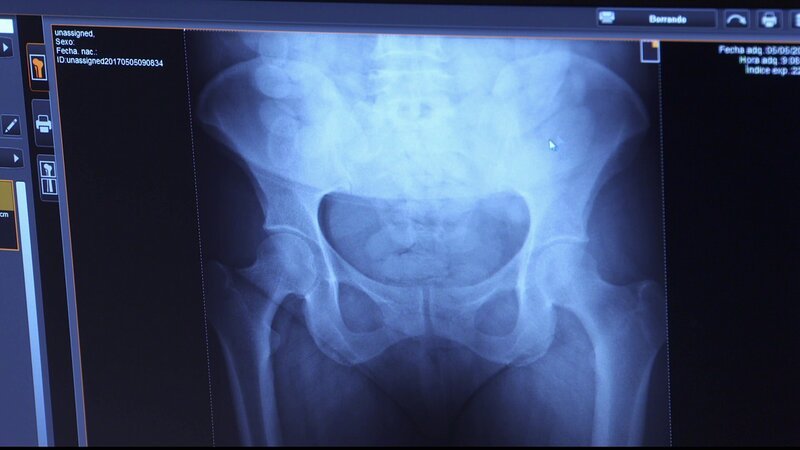

Bild: CINE NATURALEZA Y TELEVISION S.L / Discovery Communications.Madrid-Barajas International Airport: Ein Flugpassagier aus Peru erregt die Neugier der spanischen Grenzschützer. Denn beim Durchleuchten des Gepäcks sind den Beamten der Guardia Civil mehrere Flaschen mit fragwürdigem Inhalt aufgefallen. Jetzt muss ein Drogenschnelltest zeigen, was der Mannaus Lima wirklich mit sich führt. Doch die Flüssigkeiten sind nur die Spitze des Eisbergs! Später gerät im Hafen von Barcelona ein Lkw-Fahrer mit gefälschten Papieren ins Visier der Zöllner und für zwei Haschisch-Schmugglerinnen klicken die Handschellen. (Text: DMAX) Deutsche TV-Premiere Mo. 15.07.2019 DMAX Original-TV-Premiere Do. 19.10.2017 DMAX Espana